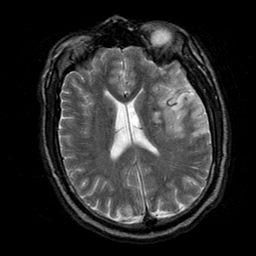

Subacute Stroke, overlay -- Slice #15

[Home][Help][Clinical] Slice 15